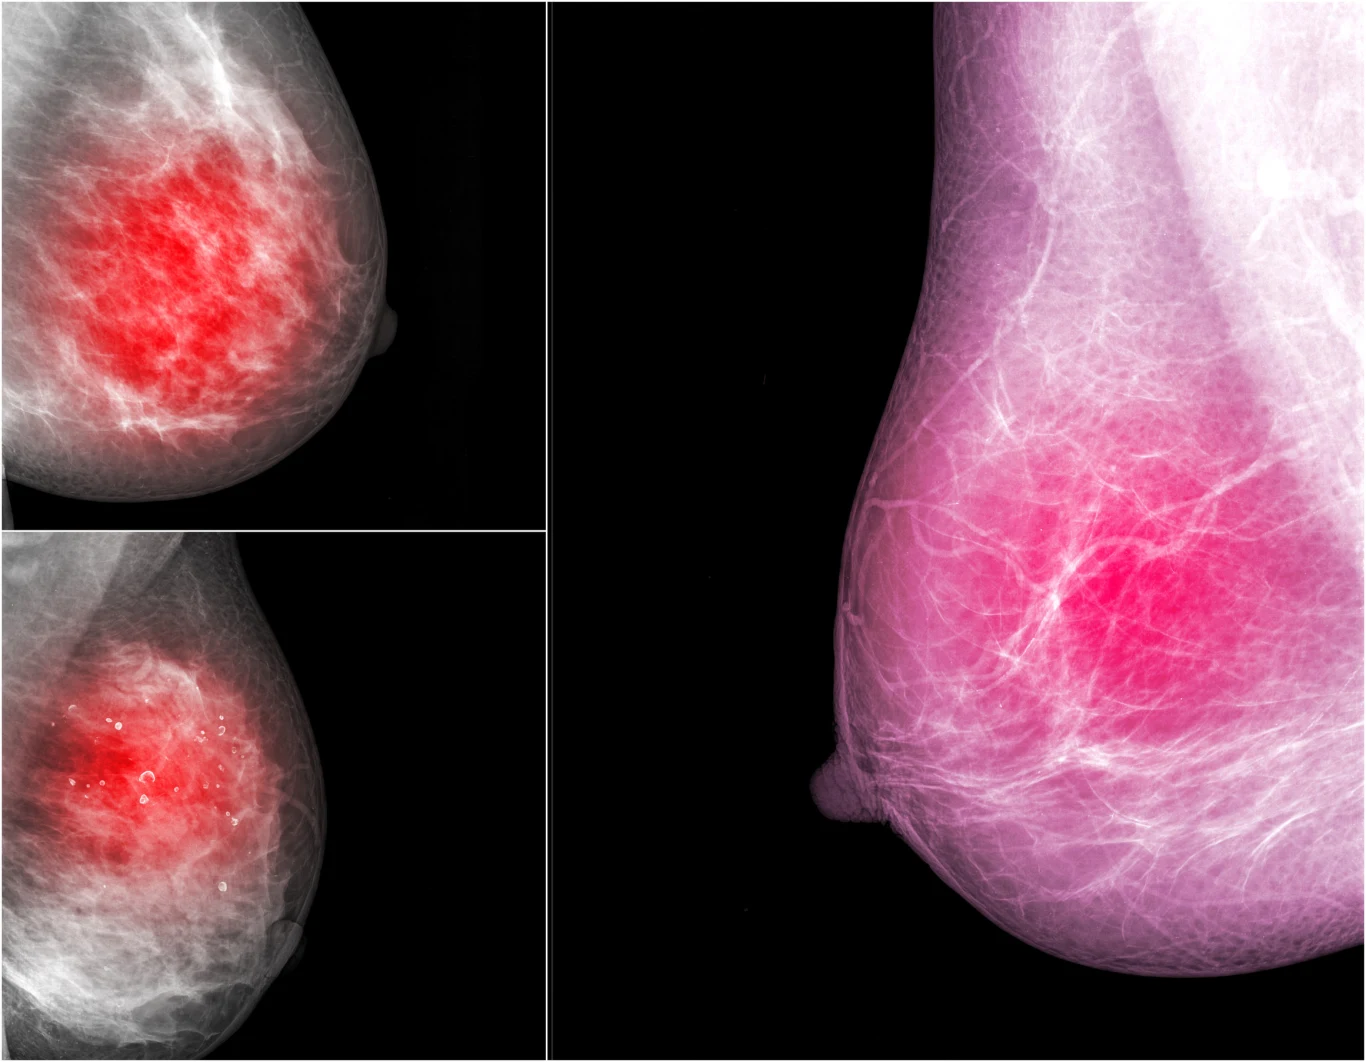

Olga nie zwlekała, umówiła się na wizytę. Miała czekać dwa tygodnie. W tak zwanym międzyczasie wybrała się na przyjęcie do znajomych. Wcale nie miała na to ochoty, a mimo to poszła. Ktoś w końcu zauważył, że jest jakaś milcząca. Podpytywana pękła i opowiedziała zebranym, co ją trapi. Obecna na spotkaniu pielęgniarka powiedziała, że tak też może się objawiać nowotwór. Olga mówi, że nie wie, jak dotarła do domu. Nazajutrz okazało się, że wizytę można przyspieszyć, jakiś pacjent zrezygnował. Zapisała się na USG. Stwierdziła, że nie zniesie więcej niepewności i domysłów. Lekarz, który wykonywał badanie, wyglądał jakby dopiero skończył studia. Przesuwał głowicą najpierw po lewej piersi - nic. Potem po prawej. Olga przysięga, że wyraz twarzy zmienił mu się natychmiast. Przeprosił pacjentkę i wyszedł do gabinetu obok, ale drzwi nie domknął, więc wszystko było słychać. Wydawał się przejęty. "Ja na tym sprzęcie jeszcze nigdy nie widziałem guza" - szepnął młody doktor do kolegi.